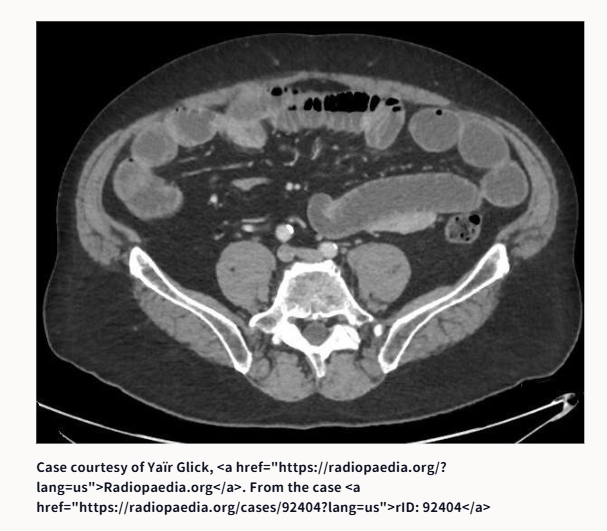

①腸閉塞です。原因は何でしょうか?

①腸閉塞の原因は、鼠径ヘルニア嵌頓でした